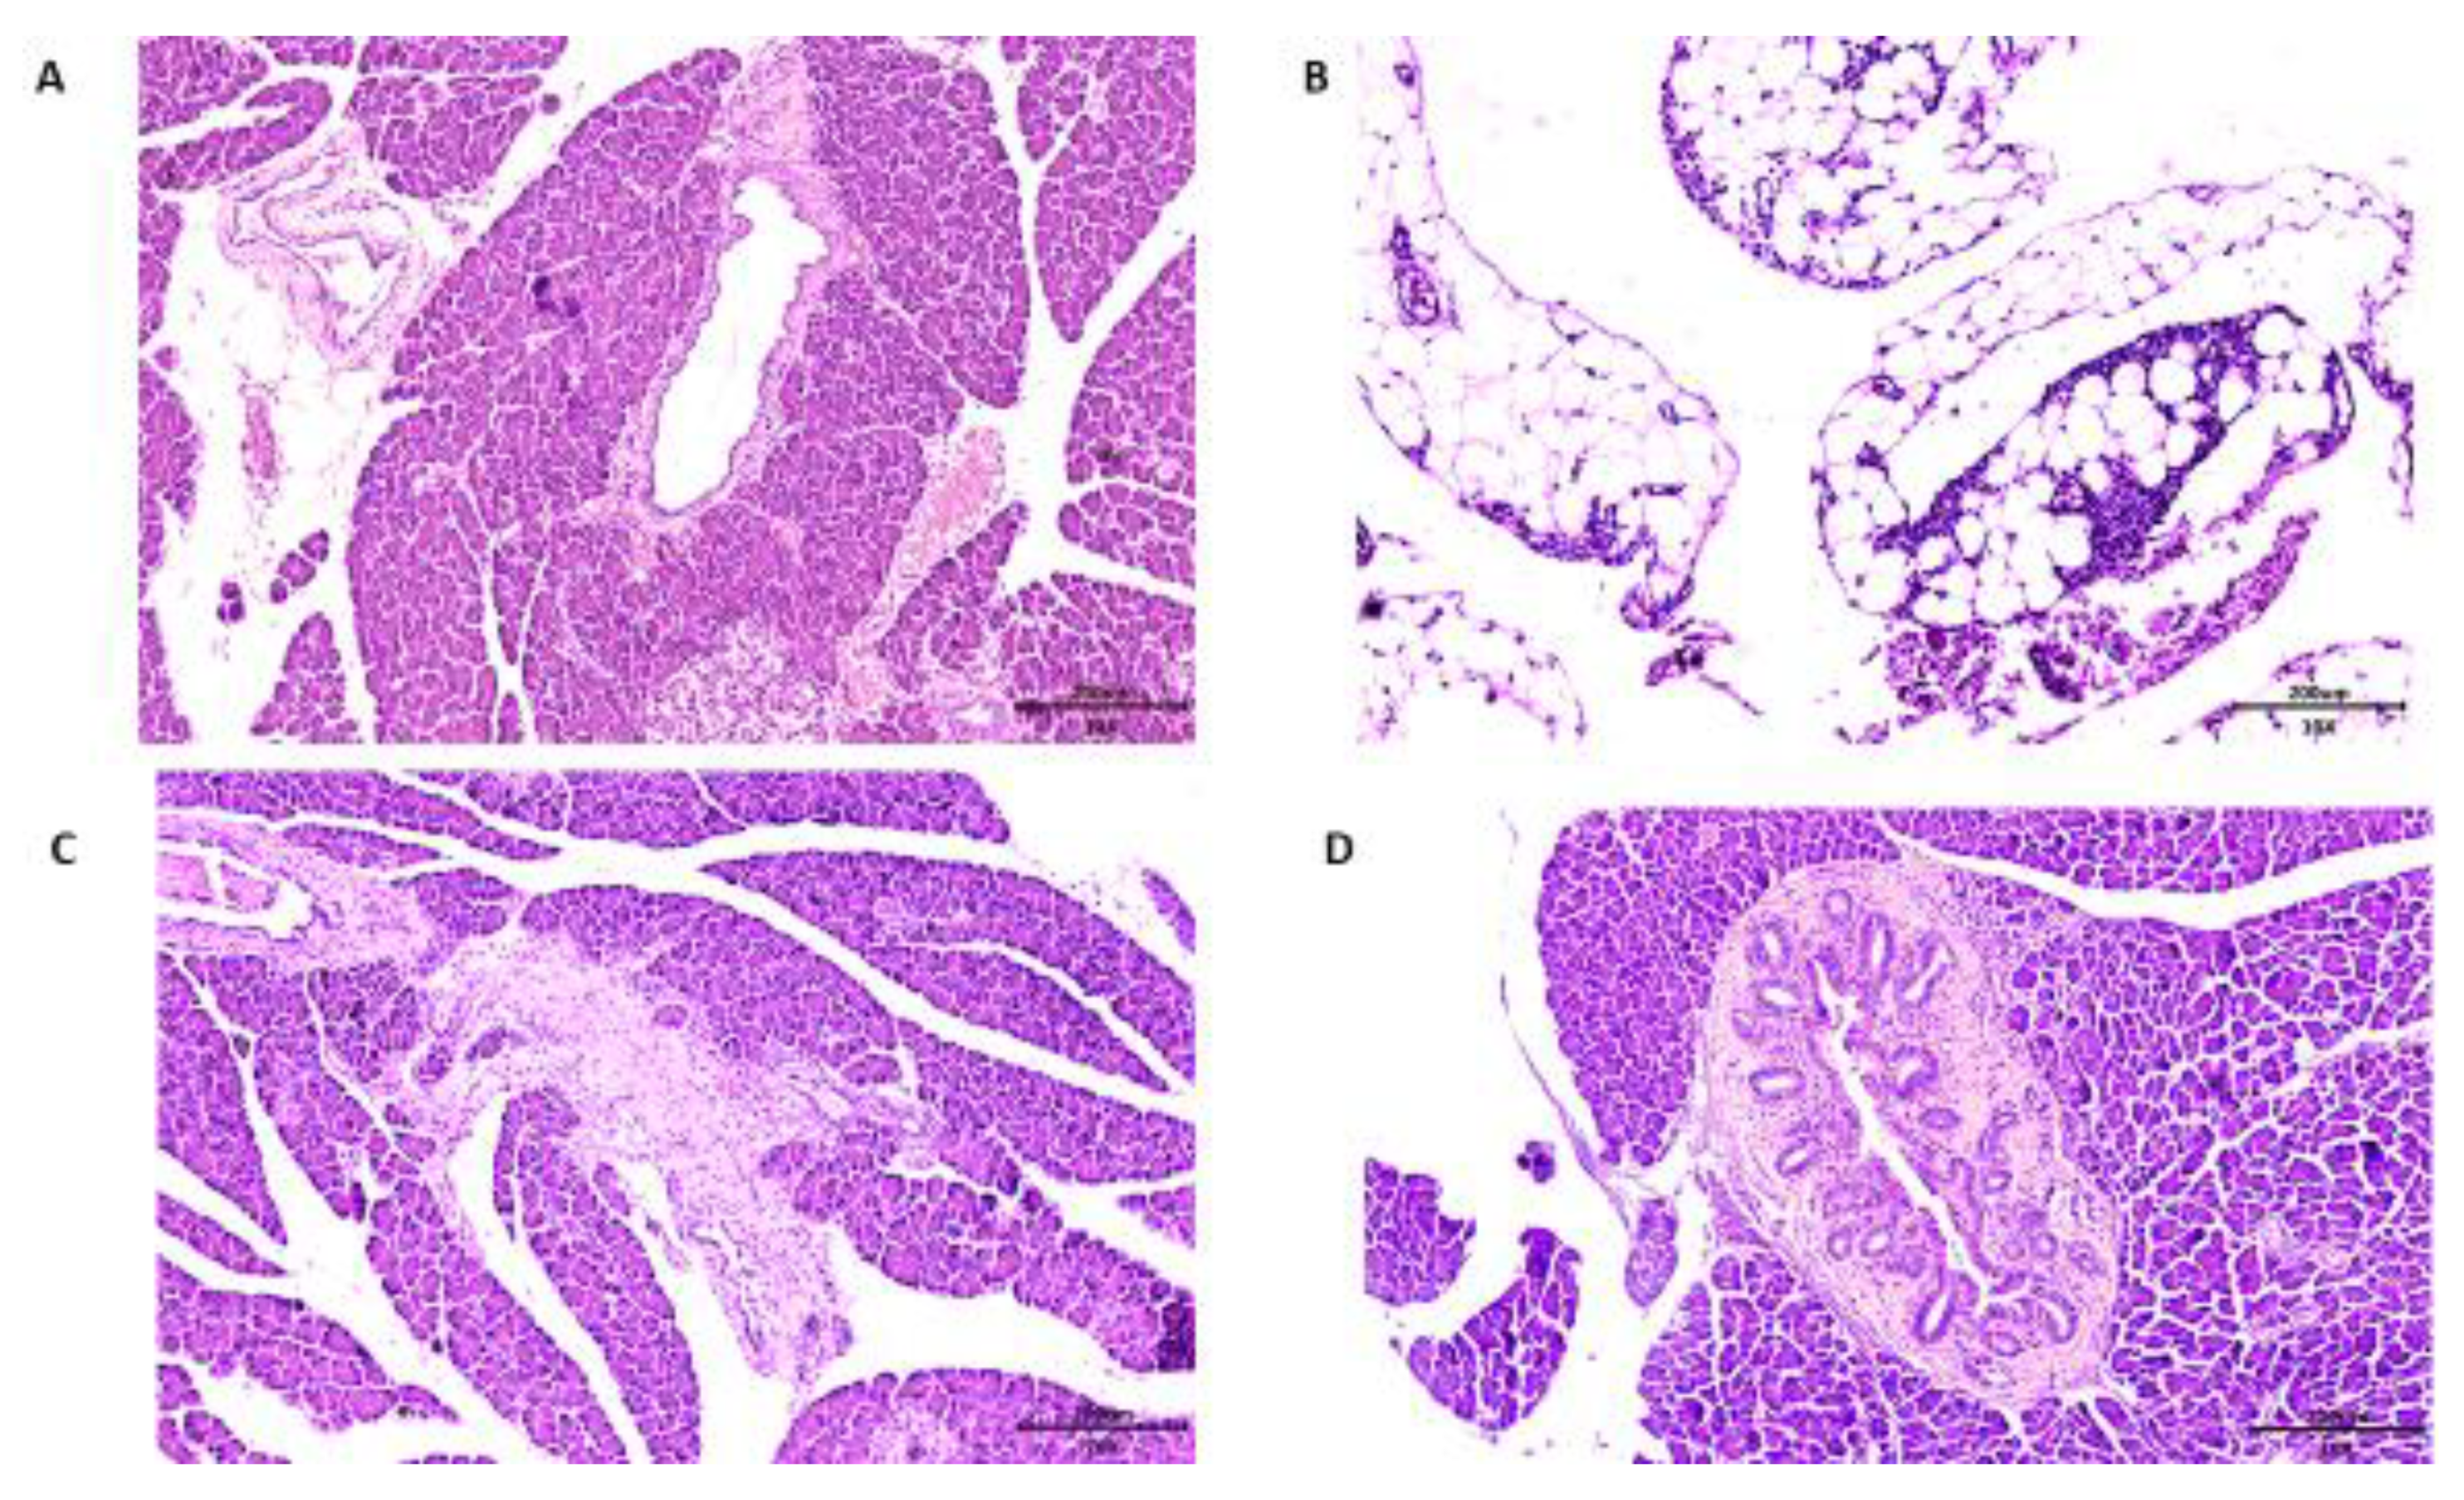

2.5.3. Microscopic Analysis of the Pancreas

3.6. Pancreas Histopathology of Wistar Rats